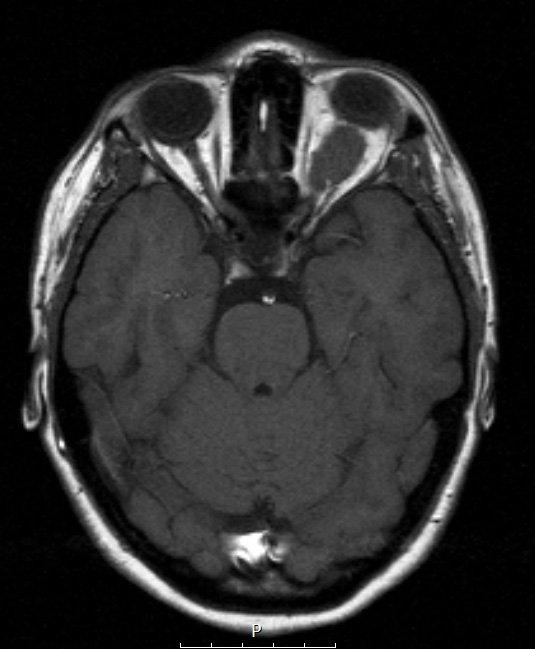

Washington University Experience | NEOPLASMS (MENINGIOMA) | Gross Pathology | 23A1 Meningioma, Optic nerve sheath (Case 23) Orbit axial T1 - Copy - Copy

Case 23 History ---- The patient was a 26-year-old woman with progressive vision loss in her left eye, accompanied by left retro-orbital pain for 8 years. Radiological imaging reveals a 2 X 1.2 cm uniformly enhancing mass in the left orbit, that appeared to track along the optic nerve, and had significantly increased in size over the last 7 years. Operative procedure: Cranio-orbital resection of left orbital / subarachnoid / optic canal mass, with orbital exenteration. ---- 23A1-3 A large optic nerve neoplasm is shown in T1-weighted absent contrast (23A1,A2) and T1-weighted with contrast (23A3)